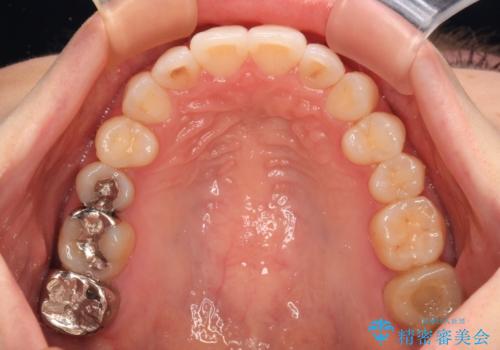

- 前歯のデコボコや八重歯の様になっていることを気にして来院された患者様です。

犬歯捻れて前方に飛び出しており、下顎前歯もそれに沿うようにデコボコとなっていました。

IPR(歯と歯の間を削る処置)によりスペースを獲得して上下顎前歯のデコボコを改善し、前歯が前方に突出しないように設定した上で、インビザラインにて矯正治療を行うこととしました。

途中体調を崩され、長い期間矯正治療を休むことになったため4年半ほどの治療期間がかかりました。